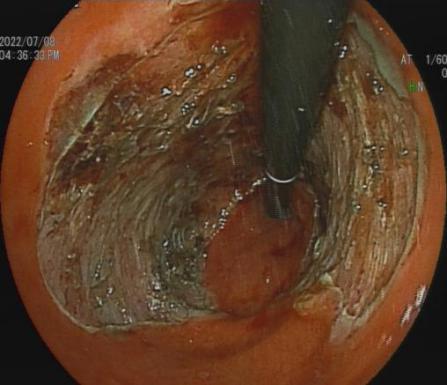

3.早期消化道肿瘤ESD技术

内镜下粘膜剥离术(ESD),具有超级微创、安全性高、住院时间短及费用低等优势,治疗早期胃癌、食管癌、大肠癌等病变,5年生存率超90%。

直肠巨大绒毛状腺瘤 内镜下粘膜剥离过程

粘膜剥离术后创面 剥离的巨大腺瘤